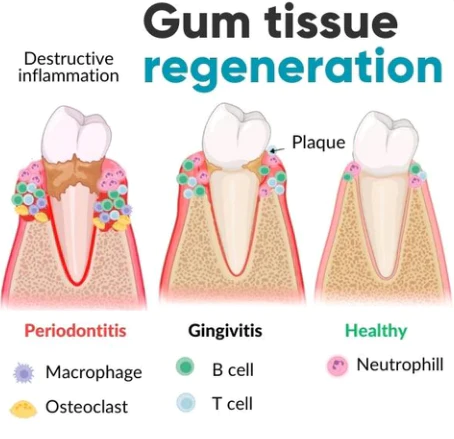

6. Gum recession

Fivfivgo™ stimulates gingival cell activity and thus promotes the regeneration of gum tissue. These active ingredients work synergistically to activate important cellular processes involved in collagen synthesis, which is essential for restoring the strength and elasticity of the gums.